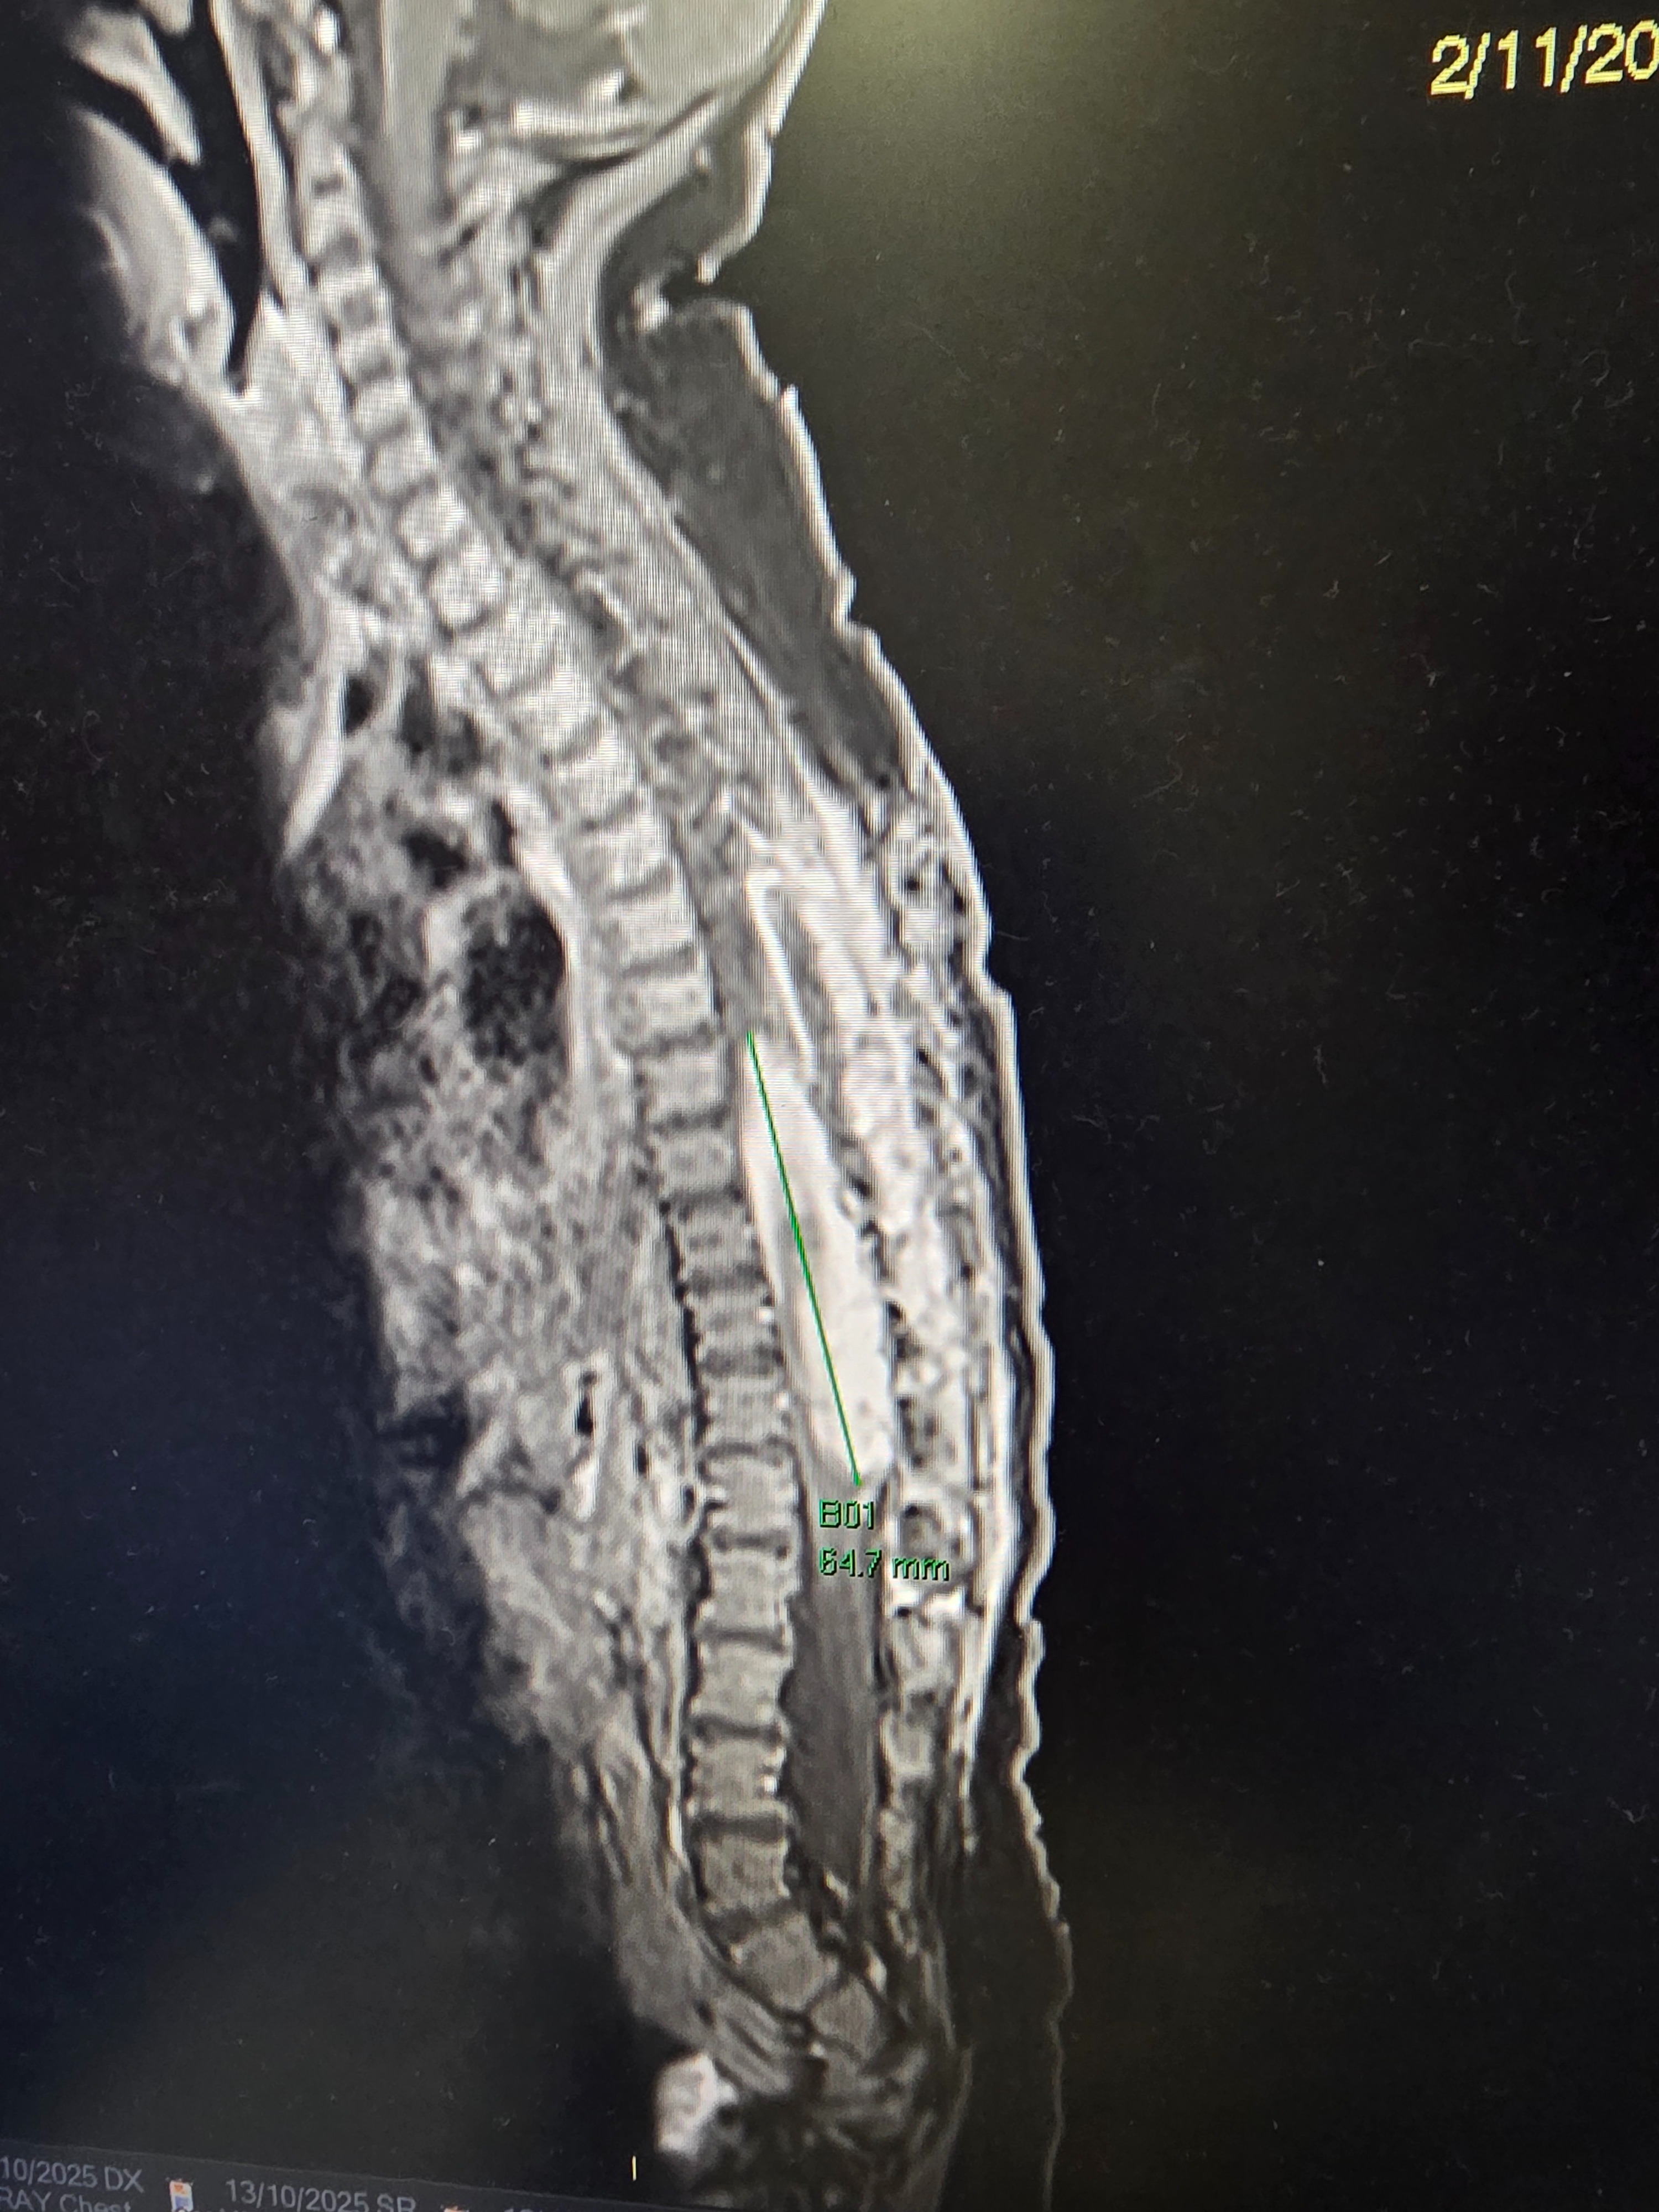

Halfway through the small hospital-garden birthday party we’d planned for him and his older brother, we were told to come immediately for his scan. We sat outside recovery waiting to see him when a doctor approached and asked if the neurosurgery team had spoken to us yet. We said no. That’s when she told us the news that shattered us completely: the tumour had regrown, larger than before — in just two weeks.

The next day — Lincolns fifth birthday — they took Jaxson back in for another major surgery.

That night was one of the hardest of our lives. But once again, our little boy came out of it strong. The surgeons believe they removed more of the tumour this time, and miraculously, he still had movement in both legs.